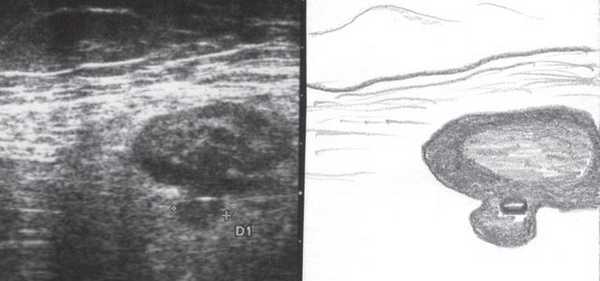

Во время контрольного УЗИ через 6 мес при осмотре левой подвздошной области толщина стенок нисходящего отдела толстой и сигмовидной кишки не превышала 3-5 мм (рис. 6, а, б), при наблюдении в течение 1 года признаков рецидива не отмечено.

Рис. 6. Эхографическая картина толстой кишки. Контрольное трансабдоминальное исследование конвексным датчиком 3,5 МГц через 6 мес.